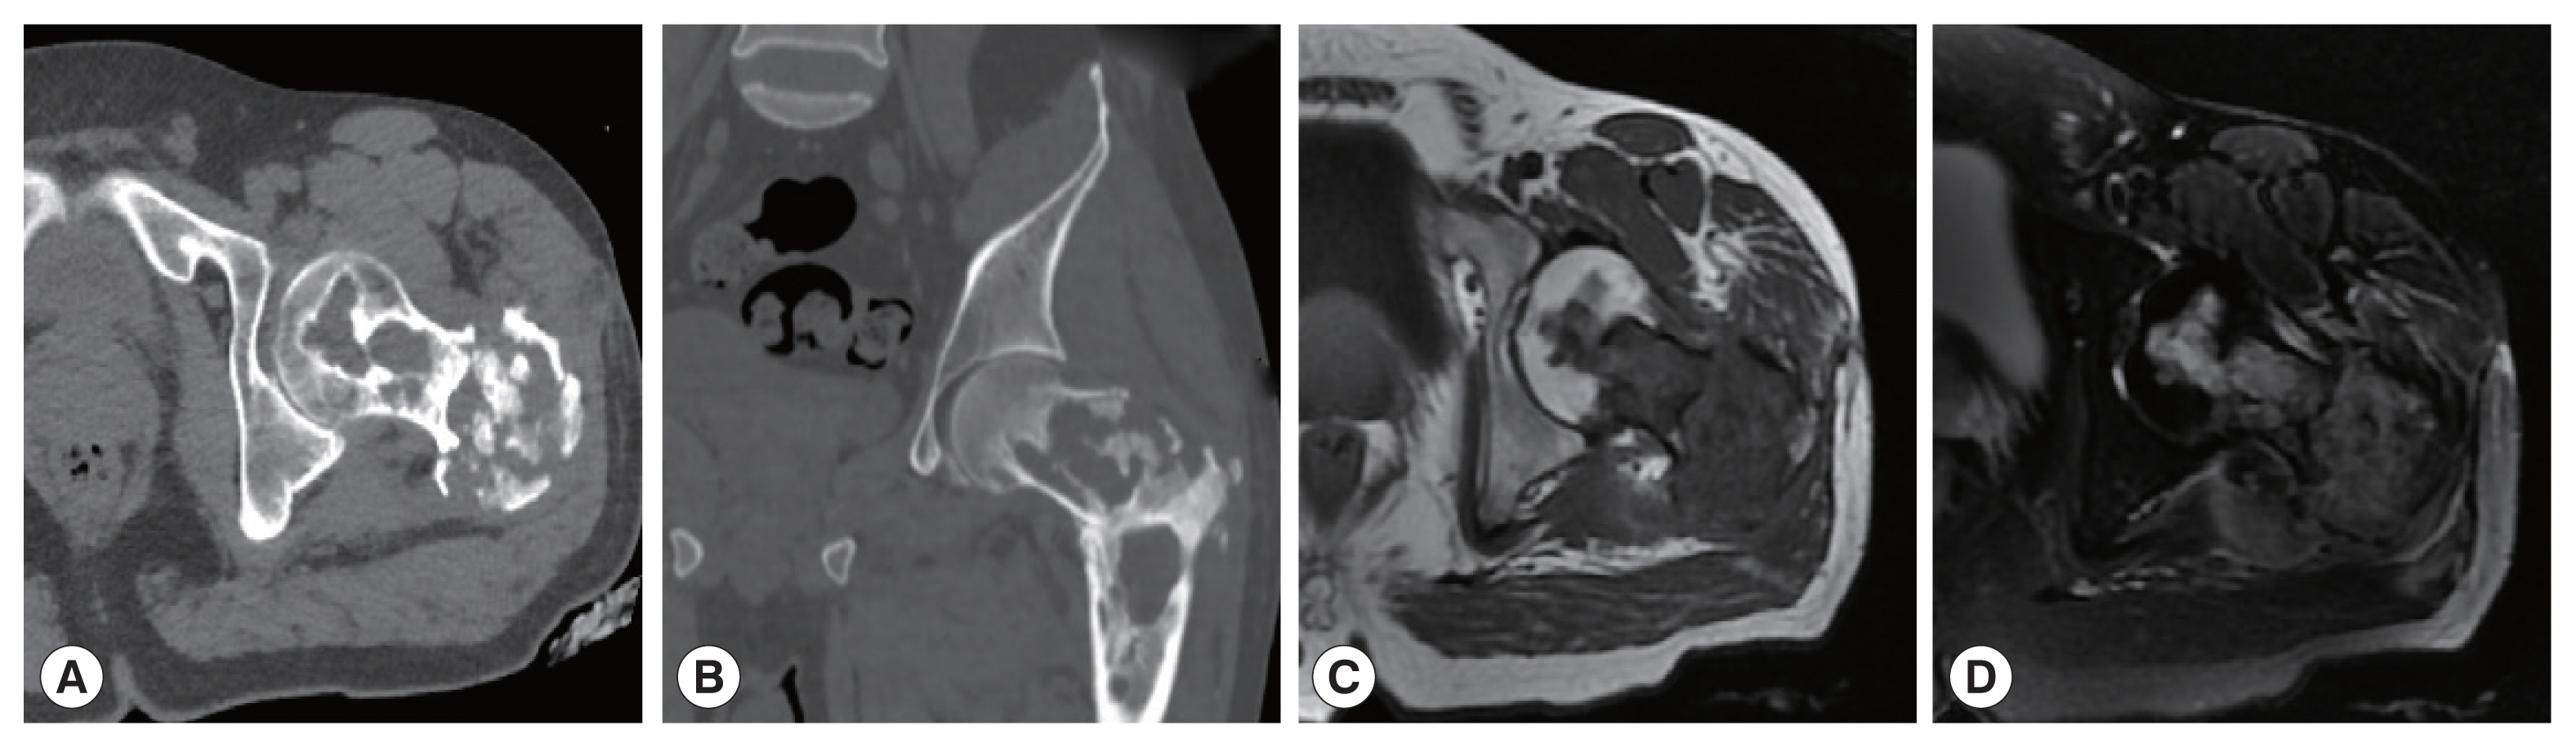

The CT images of patient 1 showed the uneven bone density and low-density bone destruction of the infected vertebral body. The boundary of the lesion was clear, but the edge was sclerotic. Multiple round low-density shadows and separation were seen, and the spinal canal was compressed and narrowed. The MRI scans also showed a low signal on T1WI, a high signal on T2WI, and a “grape bunch-like” cluster. The edge of the lesion was slightly enhanced on the enhanced scan, while no obvious enhancement was found in the interior portion. The lesion protruded into the spinal canal, causing spinal cord compression (Fig. 1). In patient 2, the lesion involving the left femoral head-femoral neck-femoral trochanter was seen on CT scan. The left femoral head, neck, and trochanter showed cystic expansive bone destruction, accompanied by sclerotic edge and dead bone formation. Local soft tissue masses were also recognized. The MRI showed an irregular low signal on T1WI, a high signal on T2WI, and a patchy high signal on T2WI in the vastus lateralis muscle (Fig. 2). Patient 3 showed osteolytic destruction of the vertebral body with wedge-shaped compression. The formation of sequestrum, intervertebral space stenosis, and swelling of the surrounding soft tissue were also noticed. In the other 3 patients (patients 4, 5, and 6), osteolytic destruction was observed, and some vertebral bodies showed wedge-shaped compression. Spinal canal stenosis and soft tissue masses were also seen locally.

One CE patient (patient 1) showed expansile bone destruction in the infected vertebral body on CT images, and polycystic changes on MR images. This patient was misdiagnosed with giant cell bone tumor. Two patients (patients 3 and 6) were misdiagnosed as tuberculosis on preoperative CT examinations because the infected vertebral body showed osteolytic bone destruction, together with sequestrum formation and soft tissue masses. Another patient (patient 4) revealed abnormal signal shadows with oval low signal on T1WI and high signal on T2WI. The patient was initially diagnosed with a neurogenic tumor due to edge enhancement on the enhanced scan.